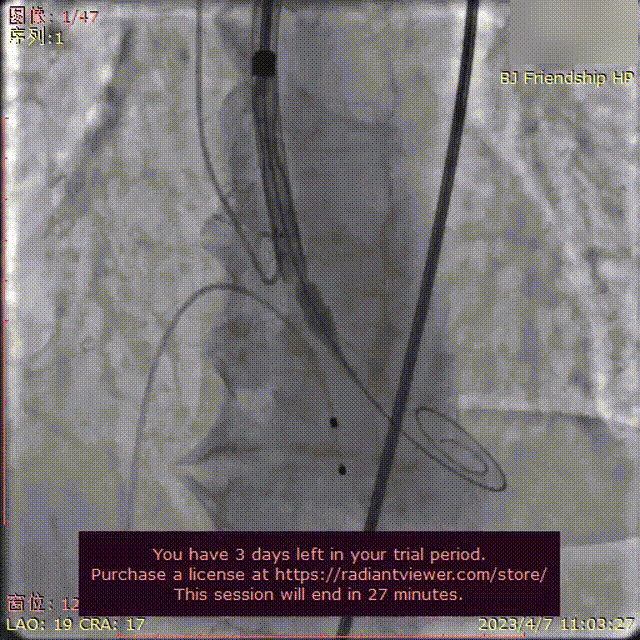

SAFARI²左室稳定定位并辅助球囊扩张和瓣膜输送定位

SAFARI²导丝轨道辅助瓣膜展开

SAFARI²辅助瓣膜定位并展开